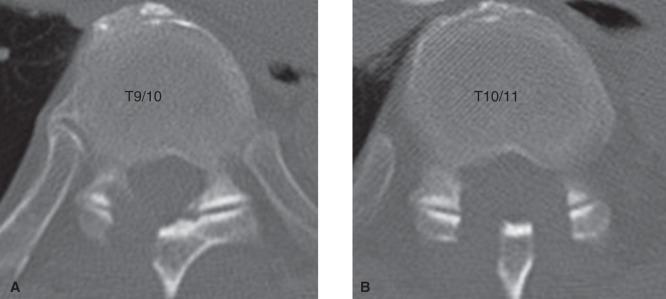

Thoracic ossification of the ligamentum flavum (OLF) has been widely recognized as a main cause of thoracic myelopathy in Asia, particularly in Japan. However, thoracic OLF rarely causes radiculopathy. We report a rare case of thoracic radiculopathy caused by OLF. A 67-year-old male presented with a chief complaint of back pain radiating to the right of the abdomen. Neurological examination revealed mild sensory deficit at the right side of the abdomen at the T9-10 level. Magnetic resonance imaging and computed tomography demonstrated OLF at the right T9-10 level. Thoracic radiculopathy caused by OLF was suspected. Because conservative treatment was not effective to this lesion, surgical intervention was performed, and the pain disappeared immediately after the operation. Thoracic OLF rarely causes radiculopathy, but it should be considered as a differential diagnosis of thoracic radicular pain. When conservative treatment is not effective in this lesion, surgical treatment should be considered.

黄韧带骨化(OLF)导致的胸椎管狭窄症在亚洲(尤其是日本)已被广泛认为是胸脊髓病的主要病因。然而,胸段 OLF 很少引起根性病变。我们报告了一例由 OLF 引起的罕见的胸神经根病病例。一名 67 岁男性,主要症状为腰痛并向右腹部放射。神经学检查显示 T9-10 水平右侧腹部有轻度感觉缺失。磁共振成像和计算机断层扫描显示右侧 T9-10 水平 OLF。考虑为 OLF 引起的胸神经根病。由于对该病变的保守治疗无效,因此进行了手术干预,术后疼痛立即消失。胸段 OLF 很少引起根性病变,但应将其视为胸神经根痛的鉴别诊断。当该病变的保守治疗无效时,应考虑手术治疗。